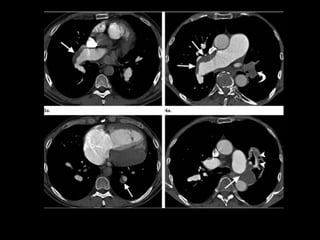

Achados de imagem: Rx e TC

Artérias pulmonares centrais dilatadas;

Trombo ocluindo e reduzindo o diâmetro da artéria

ocluída;

Localização excêntrica dos êmbolos pulmonares

com ou sem calcificações;

Estreitamento abrupto do diâmetro arterial;

Recanalização das falhas de enchimento

intraluminal;

Dilatação das artérias brônquicas.

http://radiographics.rsna.org/content/30/7/1753.full.pdf+html